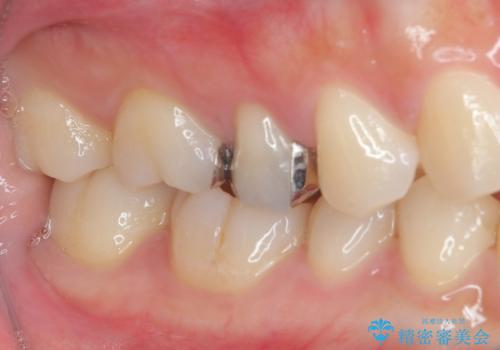

- 右上の銀歯を外したいとのことで来院された患者様です。検査後ハイブリッドインレーにて修復治療を行うことにしました。

拡大鏡視野下で銀歯、虫歯の除去を行い、ハイブリッドインレーに適した形に整えました。

ハイブリッドインレーの装着時には、唾液の侵入を防ぐために、ラバーダム防湿を行いました。